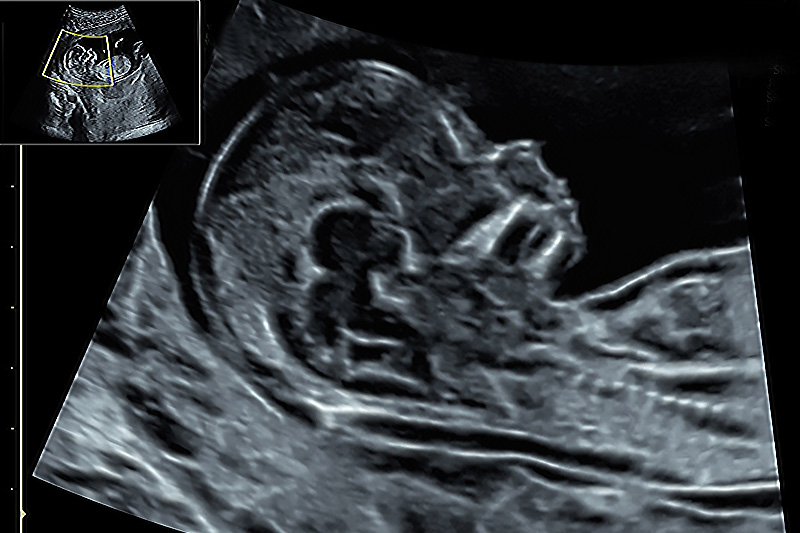

Bei der Untersuchung erfolgt eine Überprüfung des Entwicklungszustandes des Embryos und eine erste Organuntersuchung, soweit es die Verhältnisse des frühen Schwangerschaftsalters zulassen. Zahlreiche Fehlbildungen sind zu diesem Zeitpunkt bereits erkennbar, jedoch sind einige Organe (z.B. Herz, Wirbelsäule) zu diesem Zeitpunkt noch nicht abschließend beurteilbar. Eine abschließende Organbeurteilung kann erst zu einem späteren Zeitpunkt, üblicherweise in der ca. 20./22.SSW, beispielsweise über den weiterführenden Organultraschall (Feindiagnostik) erfolgen.